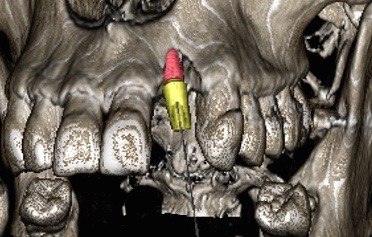

Aujourd’hui des logiciels spécifiques permettent de simuler le projet implantaire, tant pour la phase chirurgicale (pose d’un implant) que prothétique ( visualisation du pilier et de la couronne implantaires). Tous les éléments anatomiques (sinus, nerf…) qui vont se trouver à proximité du site implantaire vont être visualisés. Ces logiciels rendent donc plus sûre la pose de l’implant.

Enfin à partir de cette analyse informatique, un guide chirurgical peut-être réalisé. Ce guide est une réplique de la future prothèse dans laquelle sont ménagées des ouvertures qui vont permettre de guider le positionnement et l’axe des forets chirurgicaux garantissant ainsi le placement optimal de cet implant.